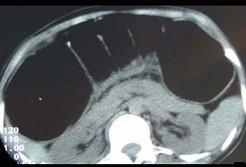

女,30岁,便秘、腹痛腹胀多年,CT检查如图,最可能的诊断是 ( )A.结肠肠梗阻B.先天性巨结肠C.结肠肠套叠D.结肠肠扭转...

问题 女,30岁,便秘、腹痛腹胀多年,CT检查如图,最可能的诊断是 ( )

选项 A.结肠肠梗阻 B.先天性巨结肠 C.结肠肠套叠 D.结肠肠扭转 E.结肠肠栓塞

答案 B